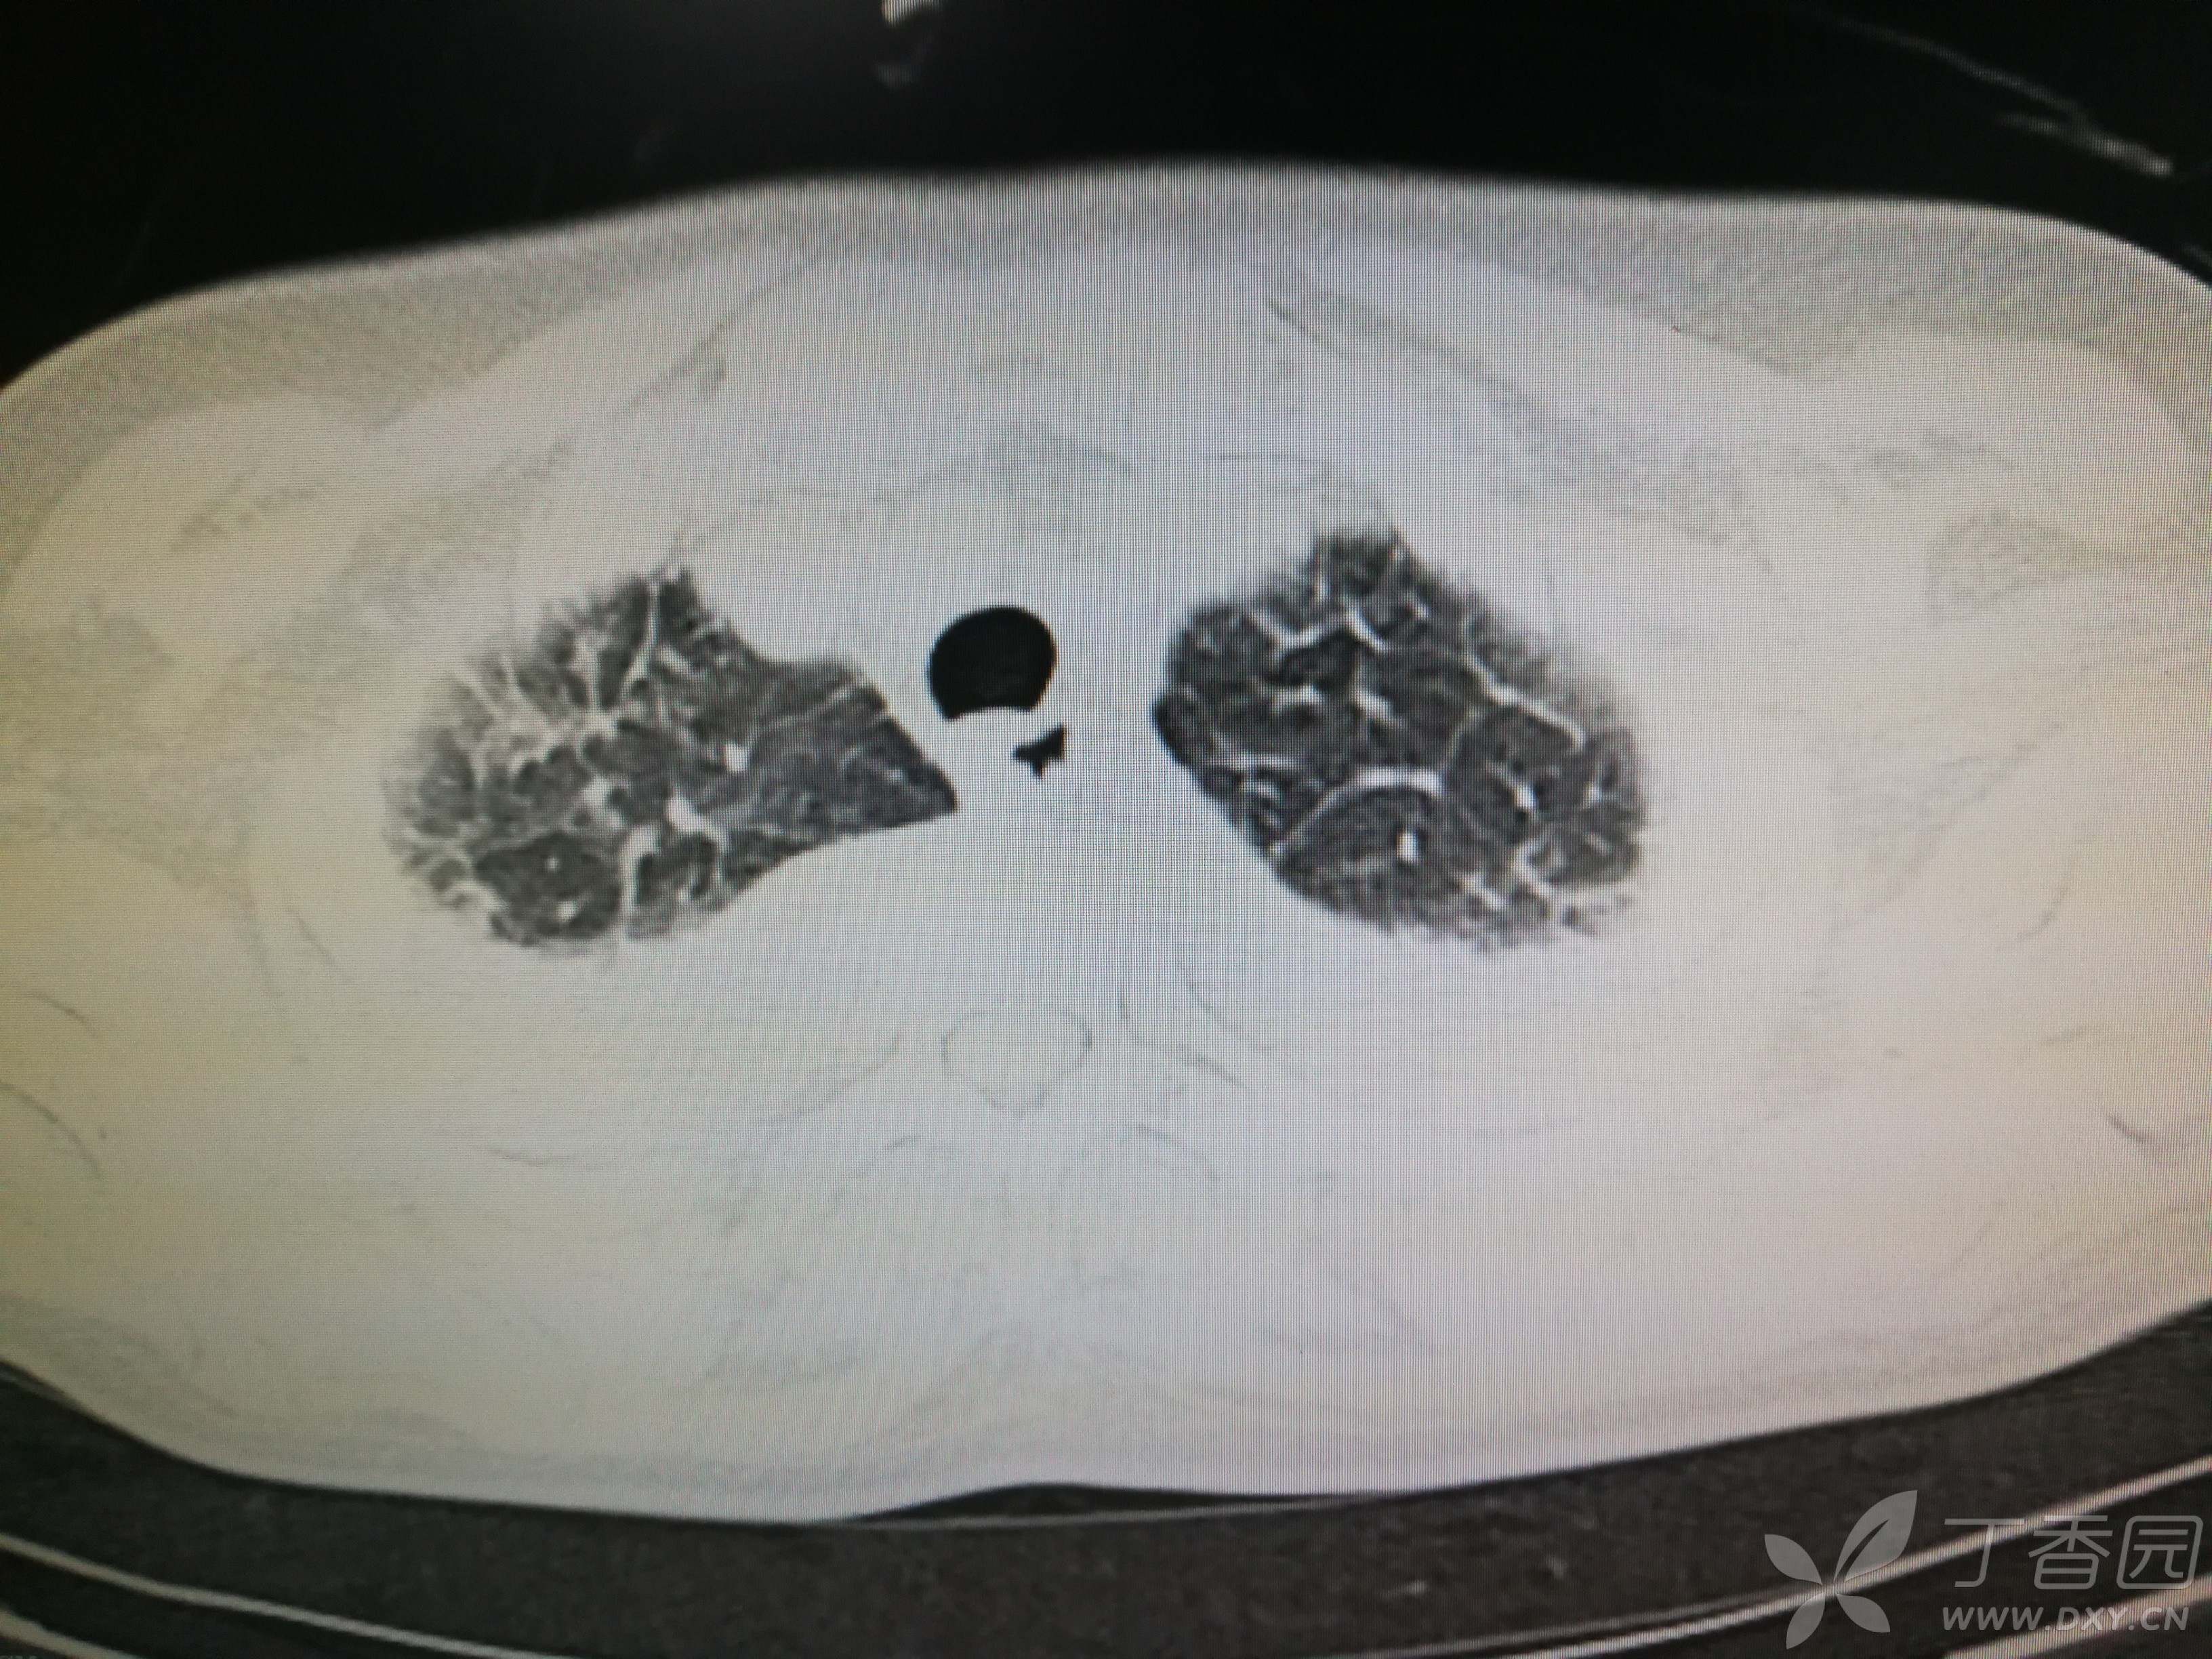

给予低分子肝素钙针抗凝、七叶皂苷钠针消肿及骨牵引固定等等治疗。入院后第四天行“左侧股骨下段骨折切开复位内固定术”(术前查双下肢彩超:双下肢深静脉血流通畅),手术顺利,术后予预防感染、预防血栓形成等治疗。术后患者无明显发热,生命体征平稳。术后第四天复查血常规:白细胞13.4×109/L,血红蛋白84g/L,血小板在正常范围。生化:白蛋白35.7g/L,余无明显异常。当天,患者开始出现轻度胸闷气急,可耐受。术后第五天患者胸闷气急加重,无胸痛,无背痛,无咯血,无意识障碍,无头晕头痛,无恶心呕吐等,急查凝血功能:纤维蛋白原降解产物12mg/L,D二聚体4000ug/L,余无明显异常。查动脉血气分析:pH7.52,氧分压62mmHg,二氧化碳分压30mmHg,碱剩余1.8mmol/L,乳酸1.0mm/L,血红蛋白86g/L。查胸部CT见下(先视频后图片):